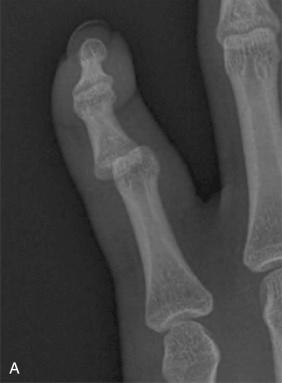

Collateral ligament injuries of the digit are much less common than those that occur at the thumb MCP joint (see the section on thumb injuries later in this chapter). Hyperabduction injuries usually occur in an ulnar direction when the finger is flexed and the ligament is taut, and hence the radial collateral ligaments (RCL) of the three ulnar-most digits are most at risk. Most hyperabduction injuries are partial injuries (grade I or II sprains) that may be treated with early active ROM and “buddy taping” to the adjacent finger for comfort. A radiograph should be obtained for all suspected collateral ligament injuries to assess for avulsion fractures. In a complete (grade III) tear, avulsion fractures may be evident, and the joint is often unstable in the coronal plane. Testing of the affected collateral ligament is performed with the MCP in flexion as that position places the collateral ligaments on maximal tension. If the joint is mechanically unstable or if an avulsion fragment displaces a substantial amount of the articular surface, an open repair is preferred. In pure ligamentous injuries or in those avulsion fractures with extremely small pieces of bone, a suture anchor works well for fixation. If the fracture fragment is large enough, we prefer to use Kirschner wires or mini fragment screw fixation ( Fig. 74.1A and B ). The avulsed fragment is on the volar half of the proximal phalanx, but we prefer a dorsal approach, as it provides excellent visualization of the entire articular surface. Immobilization of the joint in flexion (intrinsic plus or “safe” position) prevents the development of an extension contracture. For chronic tears presenting in a delayed fashion with pain and instability, temporary pinning of the MCP joint in flexion may be indicated for 2 to 3 weeks, with active motion begun thereafter. Proper diagnosis and treatment at the time of injury in important, because there is evidence that surgical repair of chronic grade III tears have inferior outcomes.

Fig. 74.1, Anteroposterior x-ray of thumb from a 31-year-old patient who fell on the radial thumb. Avulsion fracture with malrotation (A). This fracture fragment was reduced with an open approach and fixed with diverging Kirschner wires (B).